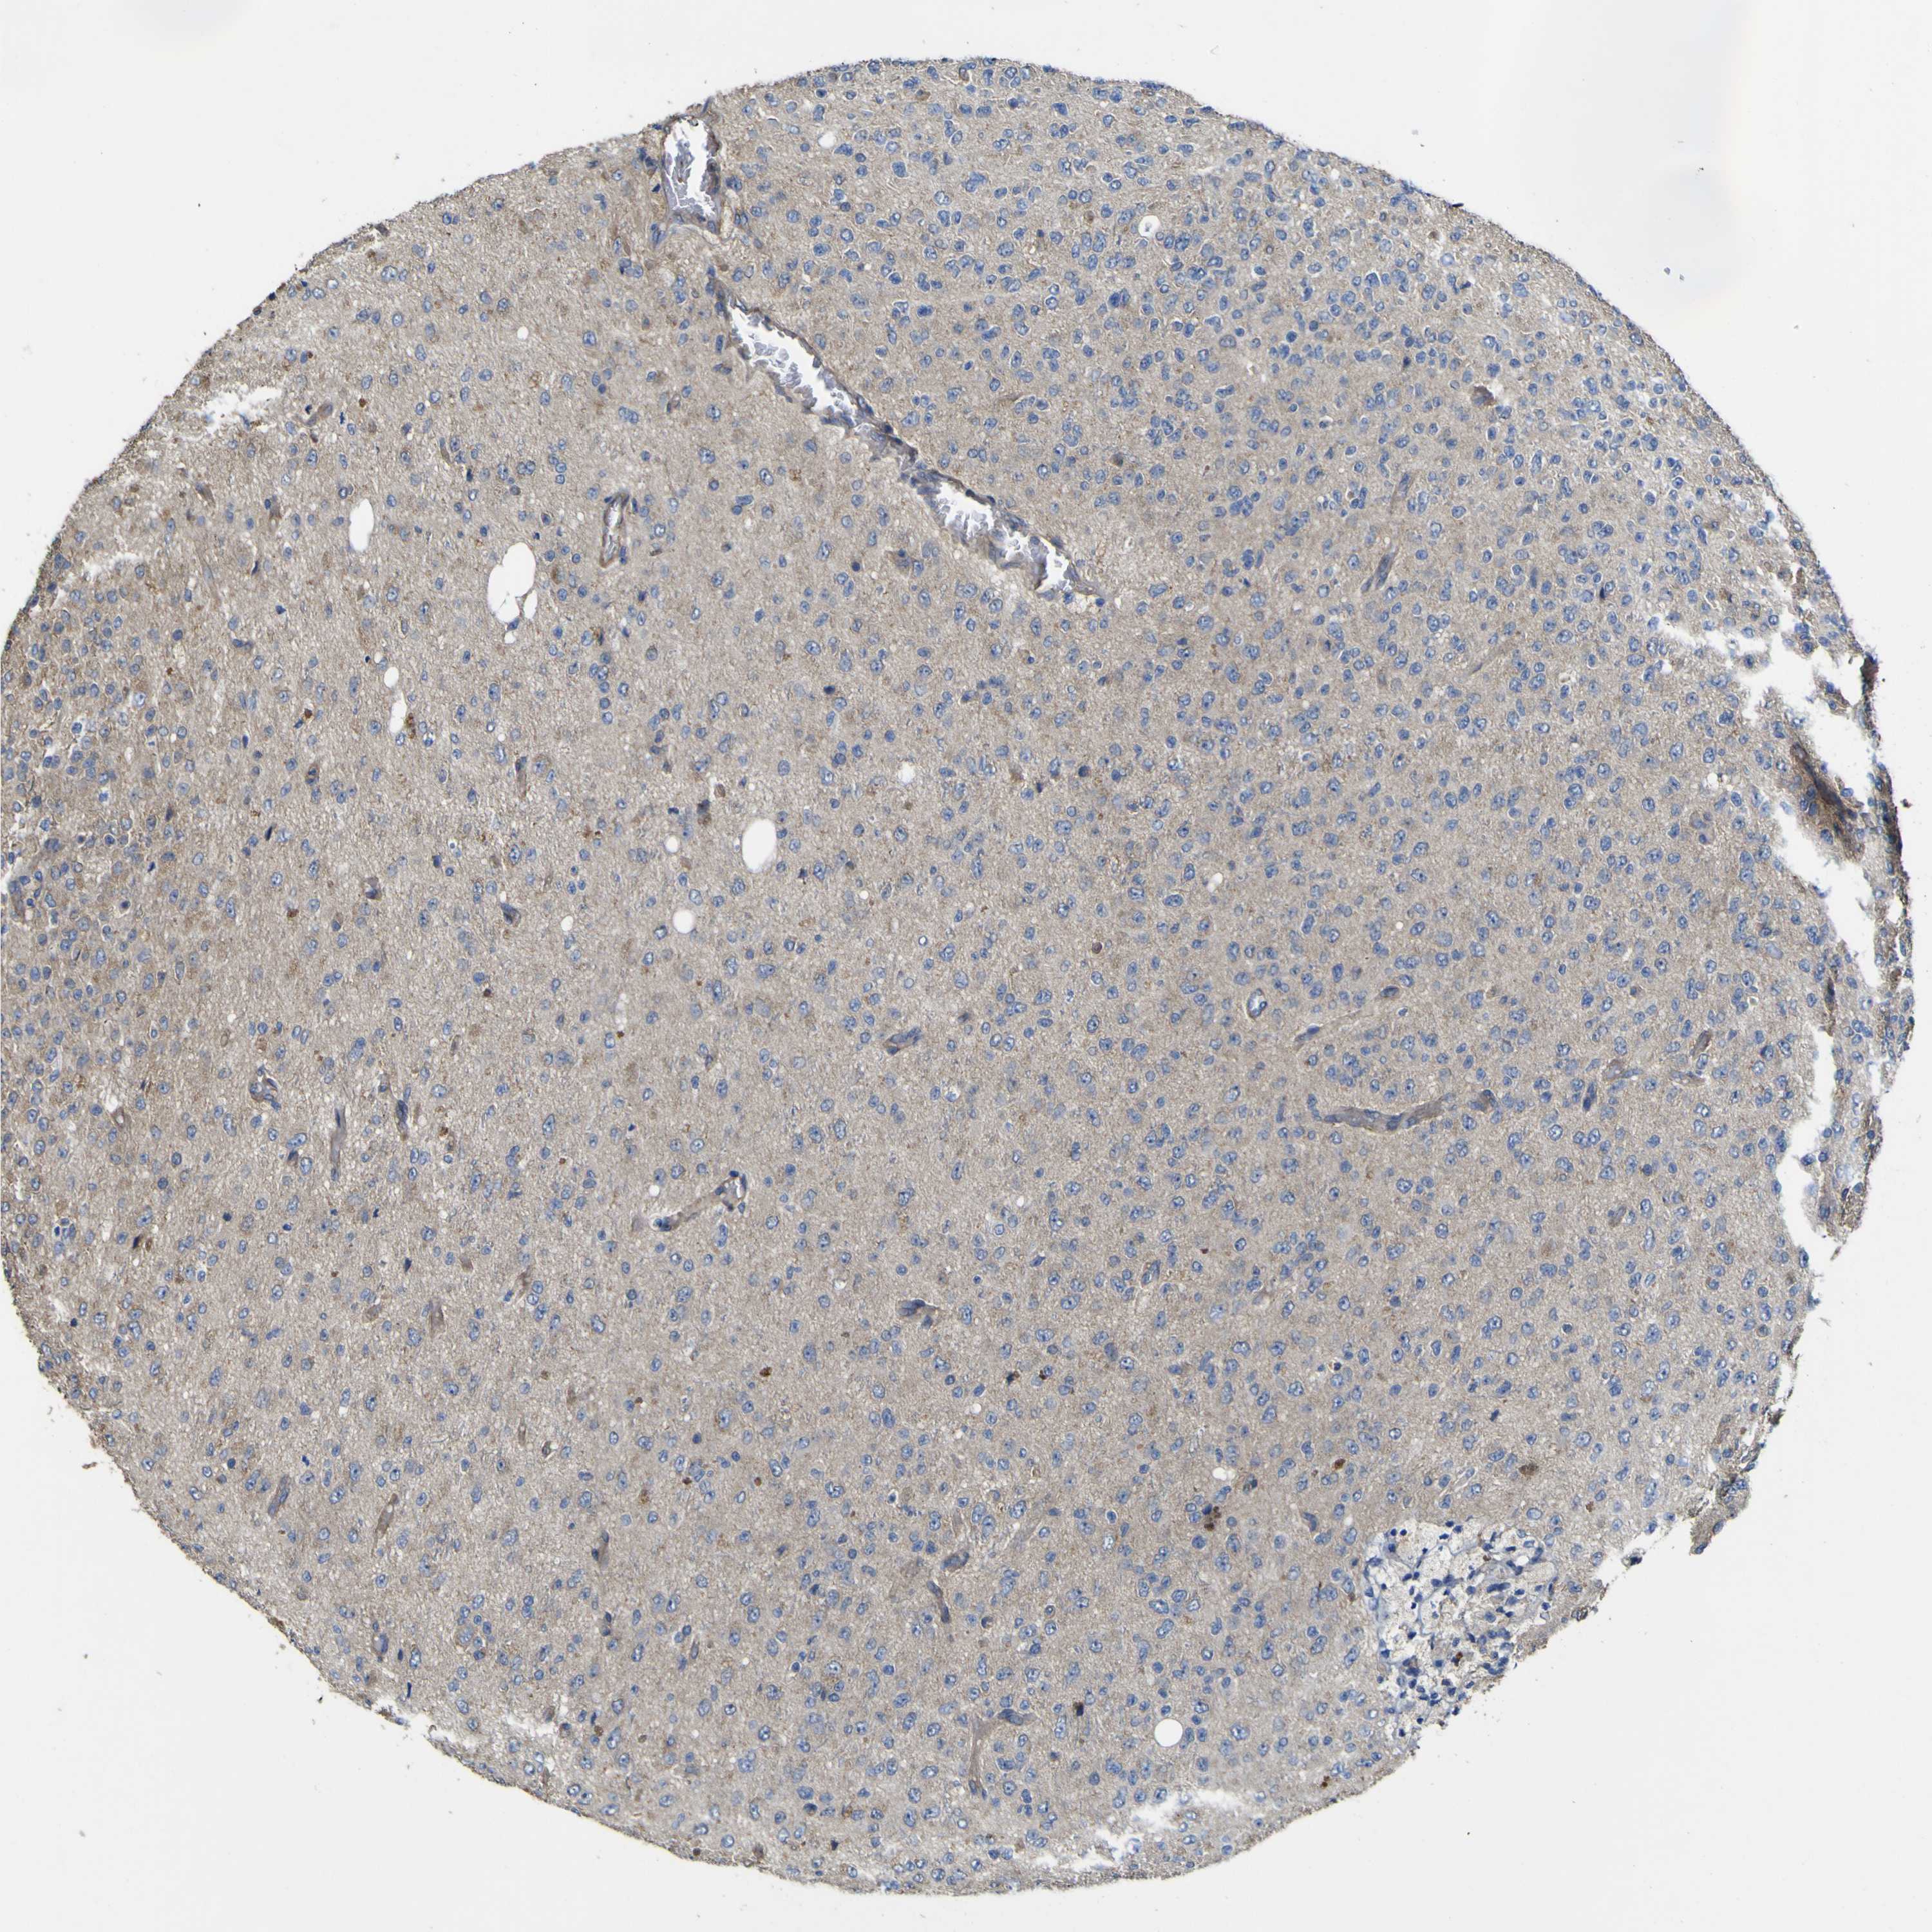

GLIOMA - Protein expressioni

A mouse-over function shows sample information and annotation data. Click on an image to view it in a full screen mode. Samples can be filtered based on level of antibody staining by selecting one or several of the following categories: high, medium, low and not detected. The assay and annotation is described here.

Note that samples used for immunohistochemistry by the Human Protein Atlas do not correspond to samples in the TCGA dataset.

Antibody stainingi

Antibody staining in the annotated cell types in the current human tissue is reported as not detected, low, medium, or high, based on conventional immunohistochemistry profiling in selected tissues. This score is based on the combination of the staining intensity and fraction of stained cells.

Each image is clickable and will lead to virtual microscopy that enables deeper exploration of all samples and also displays staining intensity scores, fraction scores and subcellular localization as well as patient and tissue information for each sample.

Antibody HPA012948

Staining

High

Medium

Low

Not detected

Intensity

Strong

Moderate

Weak

Negative

Quantity

>75%

75%-25%

<25%

None

Location

Nuclear

Cytoplasmic/membranous

Cytoplasmic/membranous,nuclear

Glioma, malignant, High grade

Glioma, malignant, Low grade